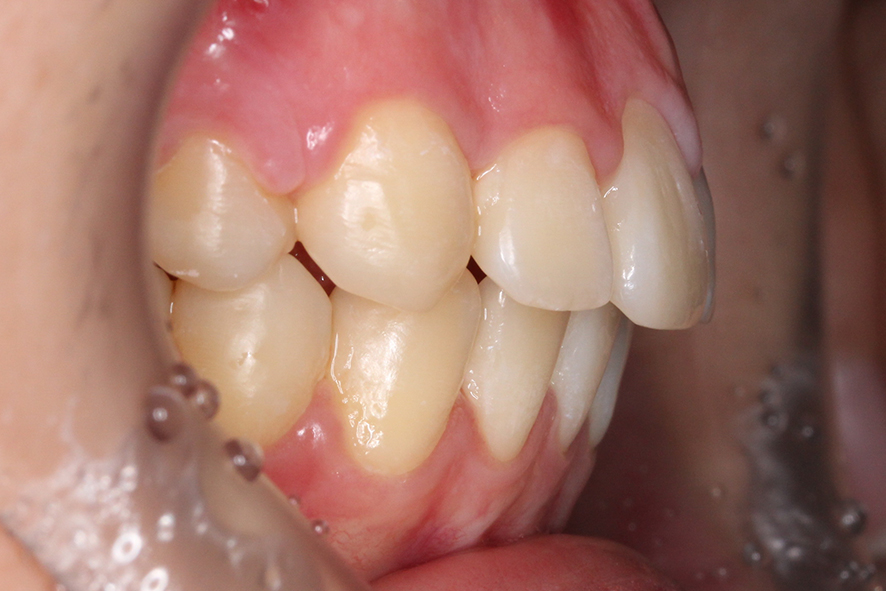

치아의 교합평면을 보면 구치부의

교합 상태가 정상적인 치아교합과

다른 모습을 확인할 수 있는데요,

상악이 하악보다 앞쪽으로 나와 있어

어금니의 상하악 교합이 어긋난 모습입니다.

반대쪽 교합 평면 또한 상악 악궁의 길이가 길고

과도하게 발달하였기 때문에 어금니의

위치가 앞쪽으로 밀려나듯이 교합되는 모습입니다.